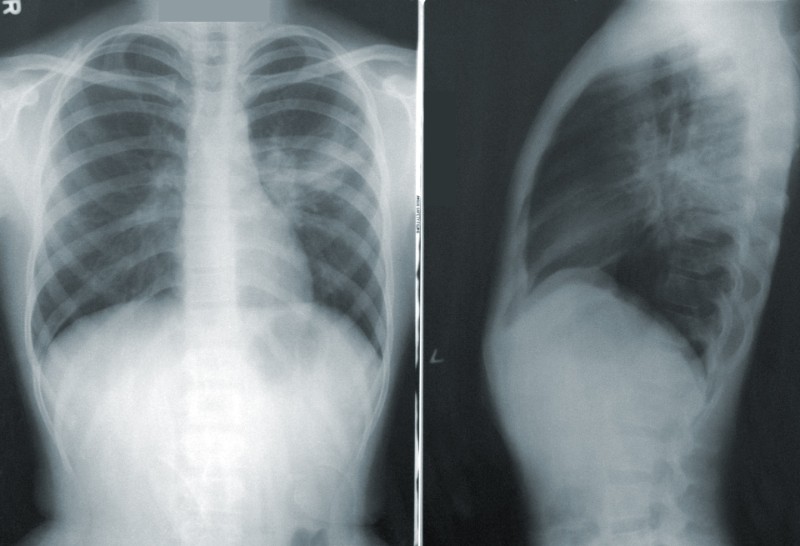

X-rays used to scan bones and other body parts expose humans to a small amount of extra radiation. In large doses, radiation exposure can lead to higher cancer risks and significant tissue damage.

On average, Americans receive about 3 mSv (millisieverts) of radiation over a year. A single chest x-ray exposes a patient to about 0.1 mSv.